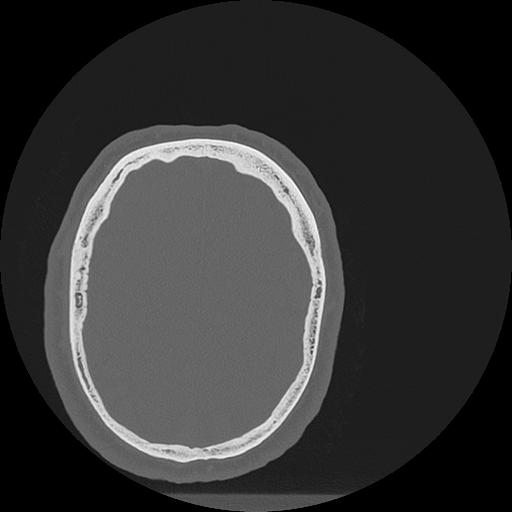

7 HUESO,,Vol,0.5,HUESO,,